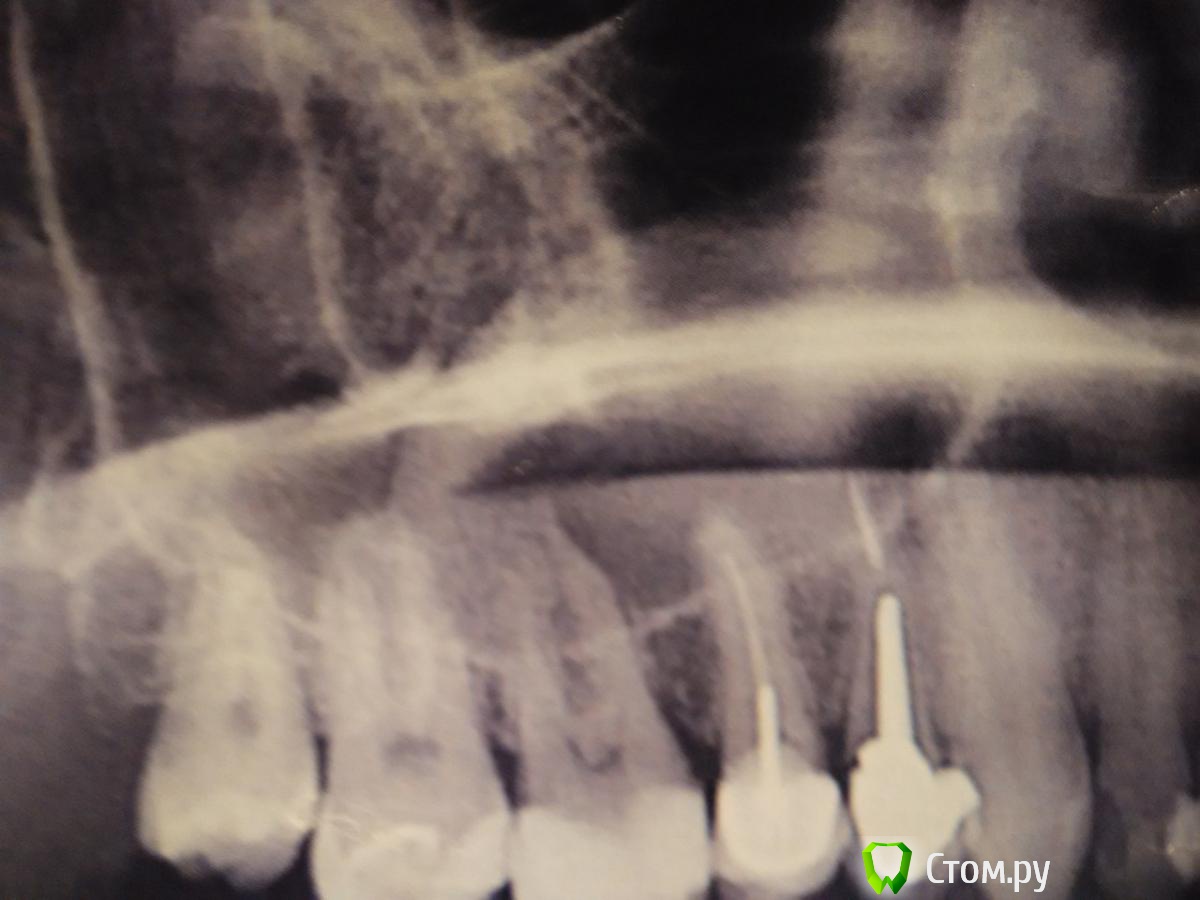

Medvedeve Опубликовано 28 августа, 2014 Поделиться Опубликовано 28 августа, 2014 (изменено) Добрый день! Я в 2010 г. удалял кисту верхнечелюстной пазухи, но спустя время опять образовалась. Консультировался с ЛОР-врачом в СПб, сказала что киста одонтогенная и необходимо разбираться с зубами. Обращался к стоматологам - разводят руками и к ЛОРу направляют обратно. Возможно Вы что-то посоветуете? В приложении направляю 1) Выписной эпикриз 2010г. после операции по удалению кисты 2) недавнее заключение по КТ 3) Ортоснимок свежий. зубы 4-ка и 5-ка под коронкой, корни уходят в верхнечелюстную пазуху. 5-ку делал еще операции 2010 года (пломбировка каналов и коронка), 4-ку не так давно. Мои подозрения на 5-ку... Скажите, если просто удалить причинный зуб может ли киста "самоликвидироваться" либо надо совмещать операции удаление зуба+удаление кисты? Основные жалобы на данный момент: напряжение и тяжесть за правой щекой, при вставании из положения лежа - болезненные ощущения в том районе (в корнях зубов), видимо гайморит еще появился. Сники КТ с программой icatvision выложил на яндекс-диск https://yadi.sk/d/BYmt_KHTaZFAZ Заранее благодарю за помощь, Евгений.эпикриз+заключение КТ.pdf Изменено 28 августа, 2014 пользователем Medvedeve Ссылка на комментарий

Bier Опубликовано 29 августа, 2014 Поделиться Опубликовано 29 августа, 2014 Какое именно из одонтогенных вы подозреваете? Симптомы характерны для кисты, это не радикулярка 1000%, какие еще варианты? мукозит? опять же симптомы не характерны . . . .можете показать срезы периапикальных областей 14,15,16? Ссылка на комментарий

dr-krasnov Опубликовано 29 августа, 2014 Поделиться Опубликовано 29 августа, 2014 http://s019.radikal.ru/i611/1408/a6/5073c8a70516.jpg http://s017.radikal.ru/i427/1408/a8/ffde2228fbd3.jpg Ссылка на комментарий

Bier Опубликовано 30 августа, 2014 Поделиться Опубликовано 30 августа, 2014 По орто есть ощущения, что каналы зубов запломбированы неудовлетворительно, а 16з уже невитальный. Я не крутил КТ (качать его долго). Если это так, то удалять зубы не нужно, но перелечить каналы надо. Потом наблюдать. Ссылка на комментарий

dr-krasnov Опубликовано 30 августа, 2014 Поделиться Опубликовано 30 августа, 2014 Странно вылил вчера изображения на радикал, сегодня не грузятся. Периапикально там все спокойно, если и есть что-то то его не видно. Ссылка на комментарий